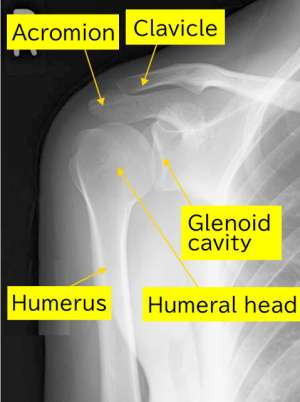

Normal

The humeral head has a rounded shape, and there is a space between the glenoid cavity and the humeral head.

Preoperative X-ray:

Significant deformation of the humerus is observed. The round shape of the humeral head is lost.